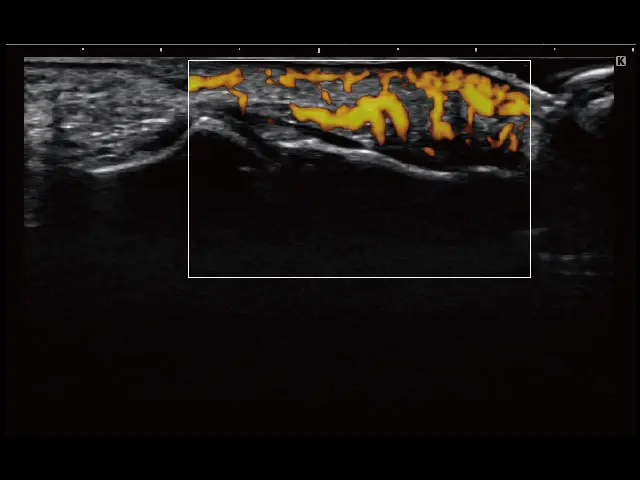

イメージギャラリー

イメージ画像を表示する